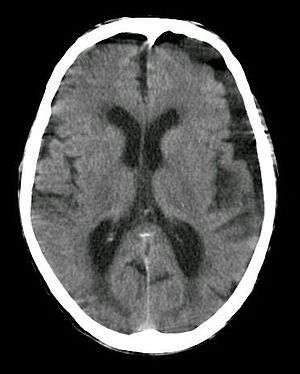

| Subdural hygroma, frontal and temporal. Man of 80 years old. | |

A subdural hygroma is a collection of cerebrospinal fluid (CSF), without blood, located under the dural membrane. Most subdural hygromas are believed to be derived from chronic subdural hematomas. They are commonly seen in elderly patients after minor trauma but can also be seen in children after an infection. One of the common causes of subdural hygroma is a sudden decrease in pressure as a result of placing a ventricular shunt. This can lead to leakage of CSF into the subdural space especially in cases with moderate to severe brain atrophy. In these cases the symptoms such as mild fever, headache, drowsiness and confusion can be seen, which are relieved by draining this subdural fluid.

In the majority of cases, if there has not been any acute trauma or severe neurologic symptoms, a small subdural hygroma on the head CT scan will be an incidental finding. If there is an associated localized mass effect that may explain the clinical symptoms, or concern for a potential chronic SDH that could rebleed, then an MRI, with or without neurologic consultation, may be useful.

It is not uncommon for chronic subdural hematomas (SDHs) on CT reports for scans of the head to be misinterpreted as subdural hygromas, and vice versa. Magnetic resonance imaging (MRI) should be done to differentiate a chronic SDH from a subdural hygroma, when clinically warranted. Elderly patients with marked cerebral atrophy, and secondary widened subarachnoid CSF spaces, can also cause confusion on CT. To distinguish chronic subdural hygromas from simple brain atrophy and CSF space expansion, a gadolinium-enhanced MRI can be performed. Visualization of cortical veins traversing the collection favors a widened subarachnoid space as seen in brain atrophy, whereas subdural hygromas will displace the cortex and cortical veins.